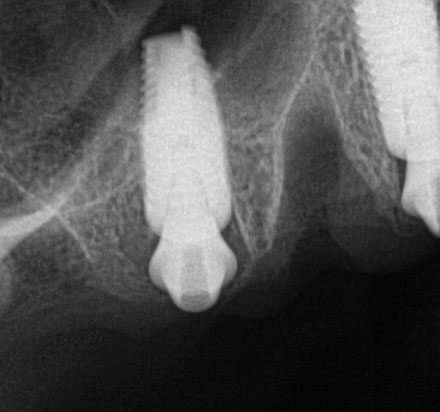

Postoperative x-rays documented the full seating of the prosthesis on the multi-unit abutments (Figure 21 and Figure 22). The patient returned at 1 week postoperatively for a follow-up visit and to review home care. She remarked that the restoration was comfortable and that she was free of discomfort and extremely pleased with the makeover she received in one day.

Fig 22. Postoperative periapical x-rays on the day of surgery demonstrating the provisional restoration with ti-bases fully seated to multi-unit abutments and ideal immediate implant placement.